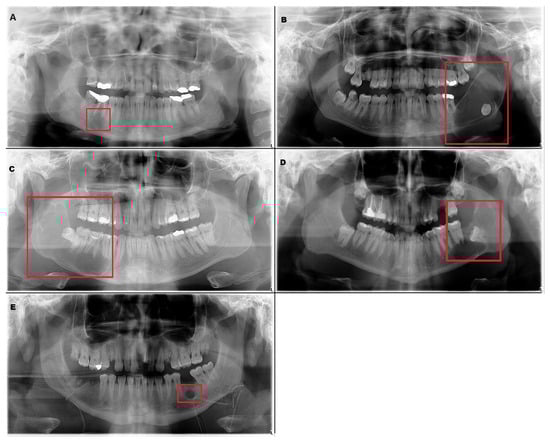

The trained model is capable of predicting bounding boxes, segmentation masks and probabilities, as shown in Figure 4 and Figure 5.

Figure 4. Model detection prediction of the radiolucent lesion in the lower jaw. (A), lesion in the ramus of the mandible (B), model successful detection of 91% (C), lesion in the corpus of the mandible (D), successful detection of 94%.